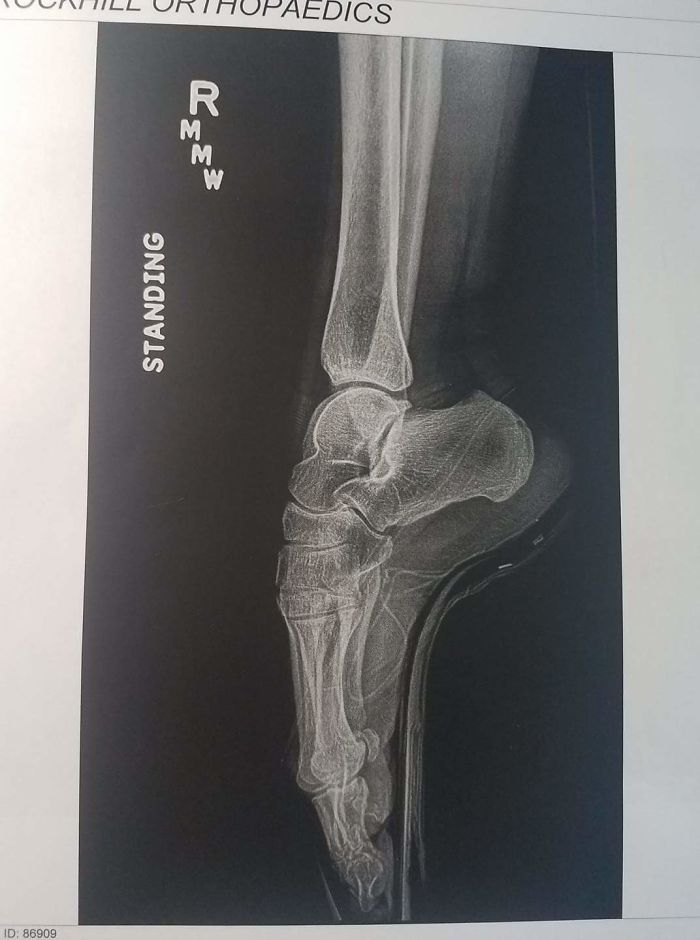

My Wife's A Ballerina, This Is Her X-Ray While En Pointe